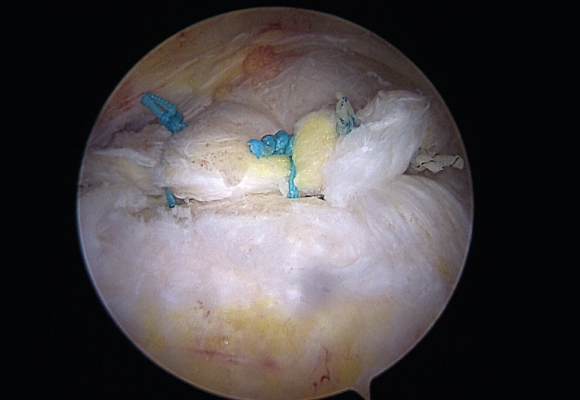

손상된 회전근개를 다듬어 주고 봉합해 주는 수술 시행

ㆍ환자의 동의를 받은 자료이며, 이미지 사진은 실물과 다를 수 있습니다. (16.09.30)